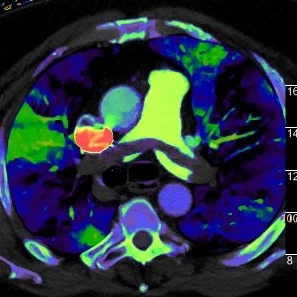

Saddle PE